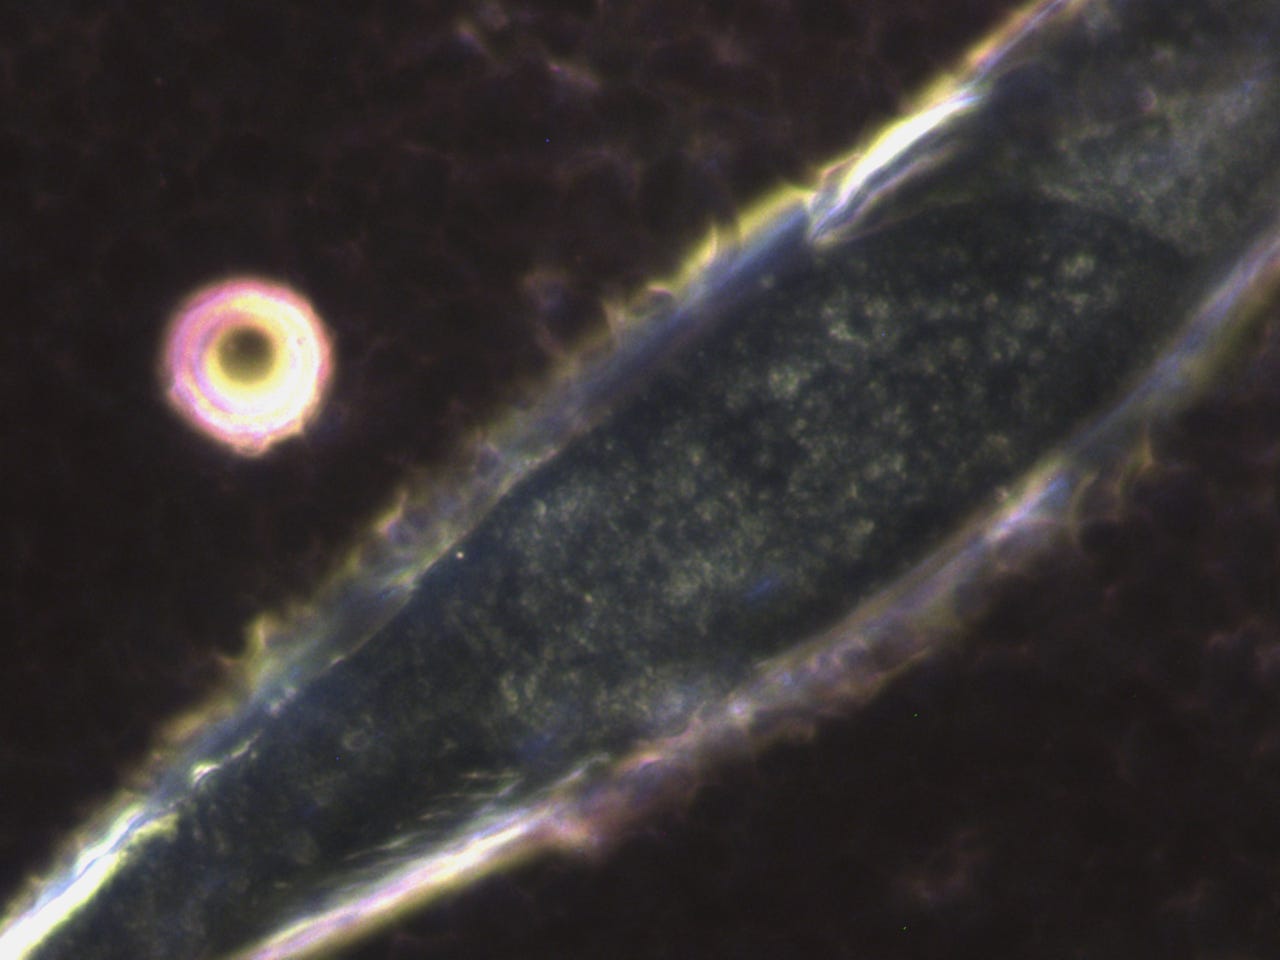

subscribed. Thank you so much. He asked to see my blood before the frequency treatments. The photo’s posted in the previous posts, especially the ones that showed the quantum dots in my blood after the MAH (Major Auto Hemotherapy) with ozone was before the frequency treatments. I am posting them here again, however, I will post some prior to that also.Quantum dots in my blood from Heparin pharmaceutical:

This was the morning after all the quantum dots destroyed my blood:

Anyway here are more before pictures;

I think these really show how messed up my blood was prior to the frequency treatments. I will always be grateful to

, Dr. David Nixon and Clifford Carnicom for their bravery and research to find what was really happening in my blood and all our blood.